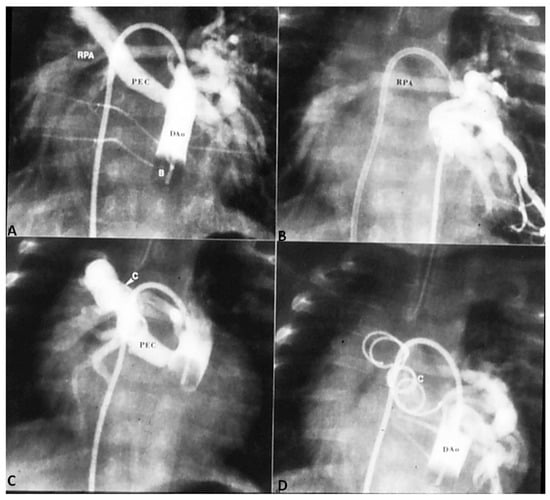

In patients with low O2 saturations and inadequate pulmonary blood flow, PGE1 infusion to open the ductus and/or an aortopulmonary shunt to augment the pulmonary blood flow may be required. In patients with adequate pulmonary blood flow with O2 saturations between 70% and 90% no immediate intervention is necessary. In patients with CHF, anti-congestive measures as detailed in Part 1 [1] should be instituted. Sometimes trans-catheter occlusion of a collateral vessel causing excessive pulmonary blood flow may needed (Figure 4) after ensuring that dual supply to the lung segments is present.